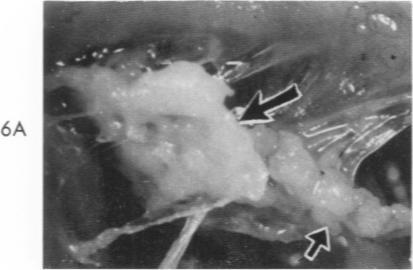

Presence of Coxiella burnetii DNA in inflamed bovine cardiac valves.